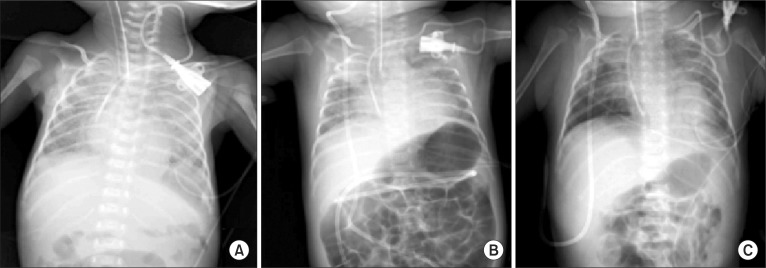

A premature female infant, weighing 1.28 kg was transferred from the local clinic, where the infant was delivered by a cesarean section at pregnant 29 weeks gestation. When transferred, she was intubated with self respiration for the management of acute respiratory distress syndrome. Two days after admission, the ventriculargaleal shunt was performed for accompanying giant hydrocephalus, under general anesthesia. After induction of anesthesia, the supraclavicular subclavian venous catheterization (SCSVC) was done at the request of the department of pediatrics. For the CVC of the infant, only the left subclavian vein was available, because the umbilical vein and the both femoral veins were obstructed or unavailable due to previous uses. Furthermore, the right central veins were to be secured by the surgeon for the protection of surgical field. The first left SCSVC (Fig. 1A) was done with 4 F double lumen entral venous catheter (Arrow Guard®, Arrow international Inc., USA) under Seldinger technique, using anatomical landmarks, and was removed after 4 weeks maintenance at neonatal intensive care unit (NICU) for the prevention of catheter-related infections. The bacterial culture of removed catheter tip was negative. Eight weeks after the first operation, when the body weight of the infant was 2.1 kg, the second same left SCSVC (Fig. 1B) was performed under general anesthesia for the ventriculoperitoneal shunt (VPS) to relieve hydrocephalus. The second catheter was removed after 3 weeks maintenance at NICU and the third left SCSVC (Fig. 1C) was carried out on the same day (when the body weight was 2.31 kg) under sedation. The third catheter was patent till the revision of VPS, which was done 4 weeks after the third CVC and the body weight of infant increased to 3.2 kg.

All CVCs were done by the same anesthesiologist, with the use of maximal barriers of infection (operation gown, sterile glove, cap, mask, and large sterile sheet drape). Instead of ultrasound (US)-guided central venous catheterization, we used the classic anatomical landmark technique for the puncture of the left subclavian vein [3]. The infant was positioned supine and 15 degree of Trendelenburg position with the arms beside the body and the head turned to the right side. Landmarks for skin puncture were the clavicosternomastoid angles, formed by the lateral head of the left sternocleidomastoid muscle and the upper border of the left clavicle. Then, the needles were introduced at this point and directed inferio-medial-posteriorly at 30-45 degree to the sagittal plane. During three times for left SCSVC, we succeeded subclavian punctures with one or two skin punctures. During and after CVC procedures, there were no remarkable changes in the vital signs, pulse oximeters and electrocardiograms. The central venous catheters were advanced about 6-7 cm from the skin and confirmed the intraatrial positioning by the follow up chest radiography.